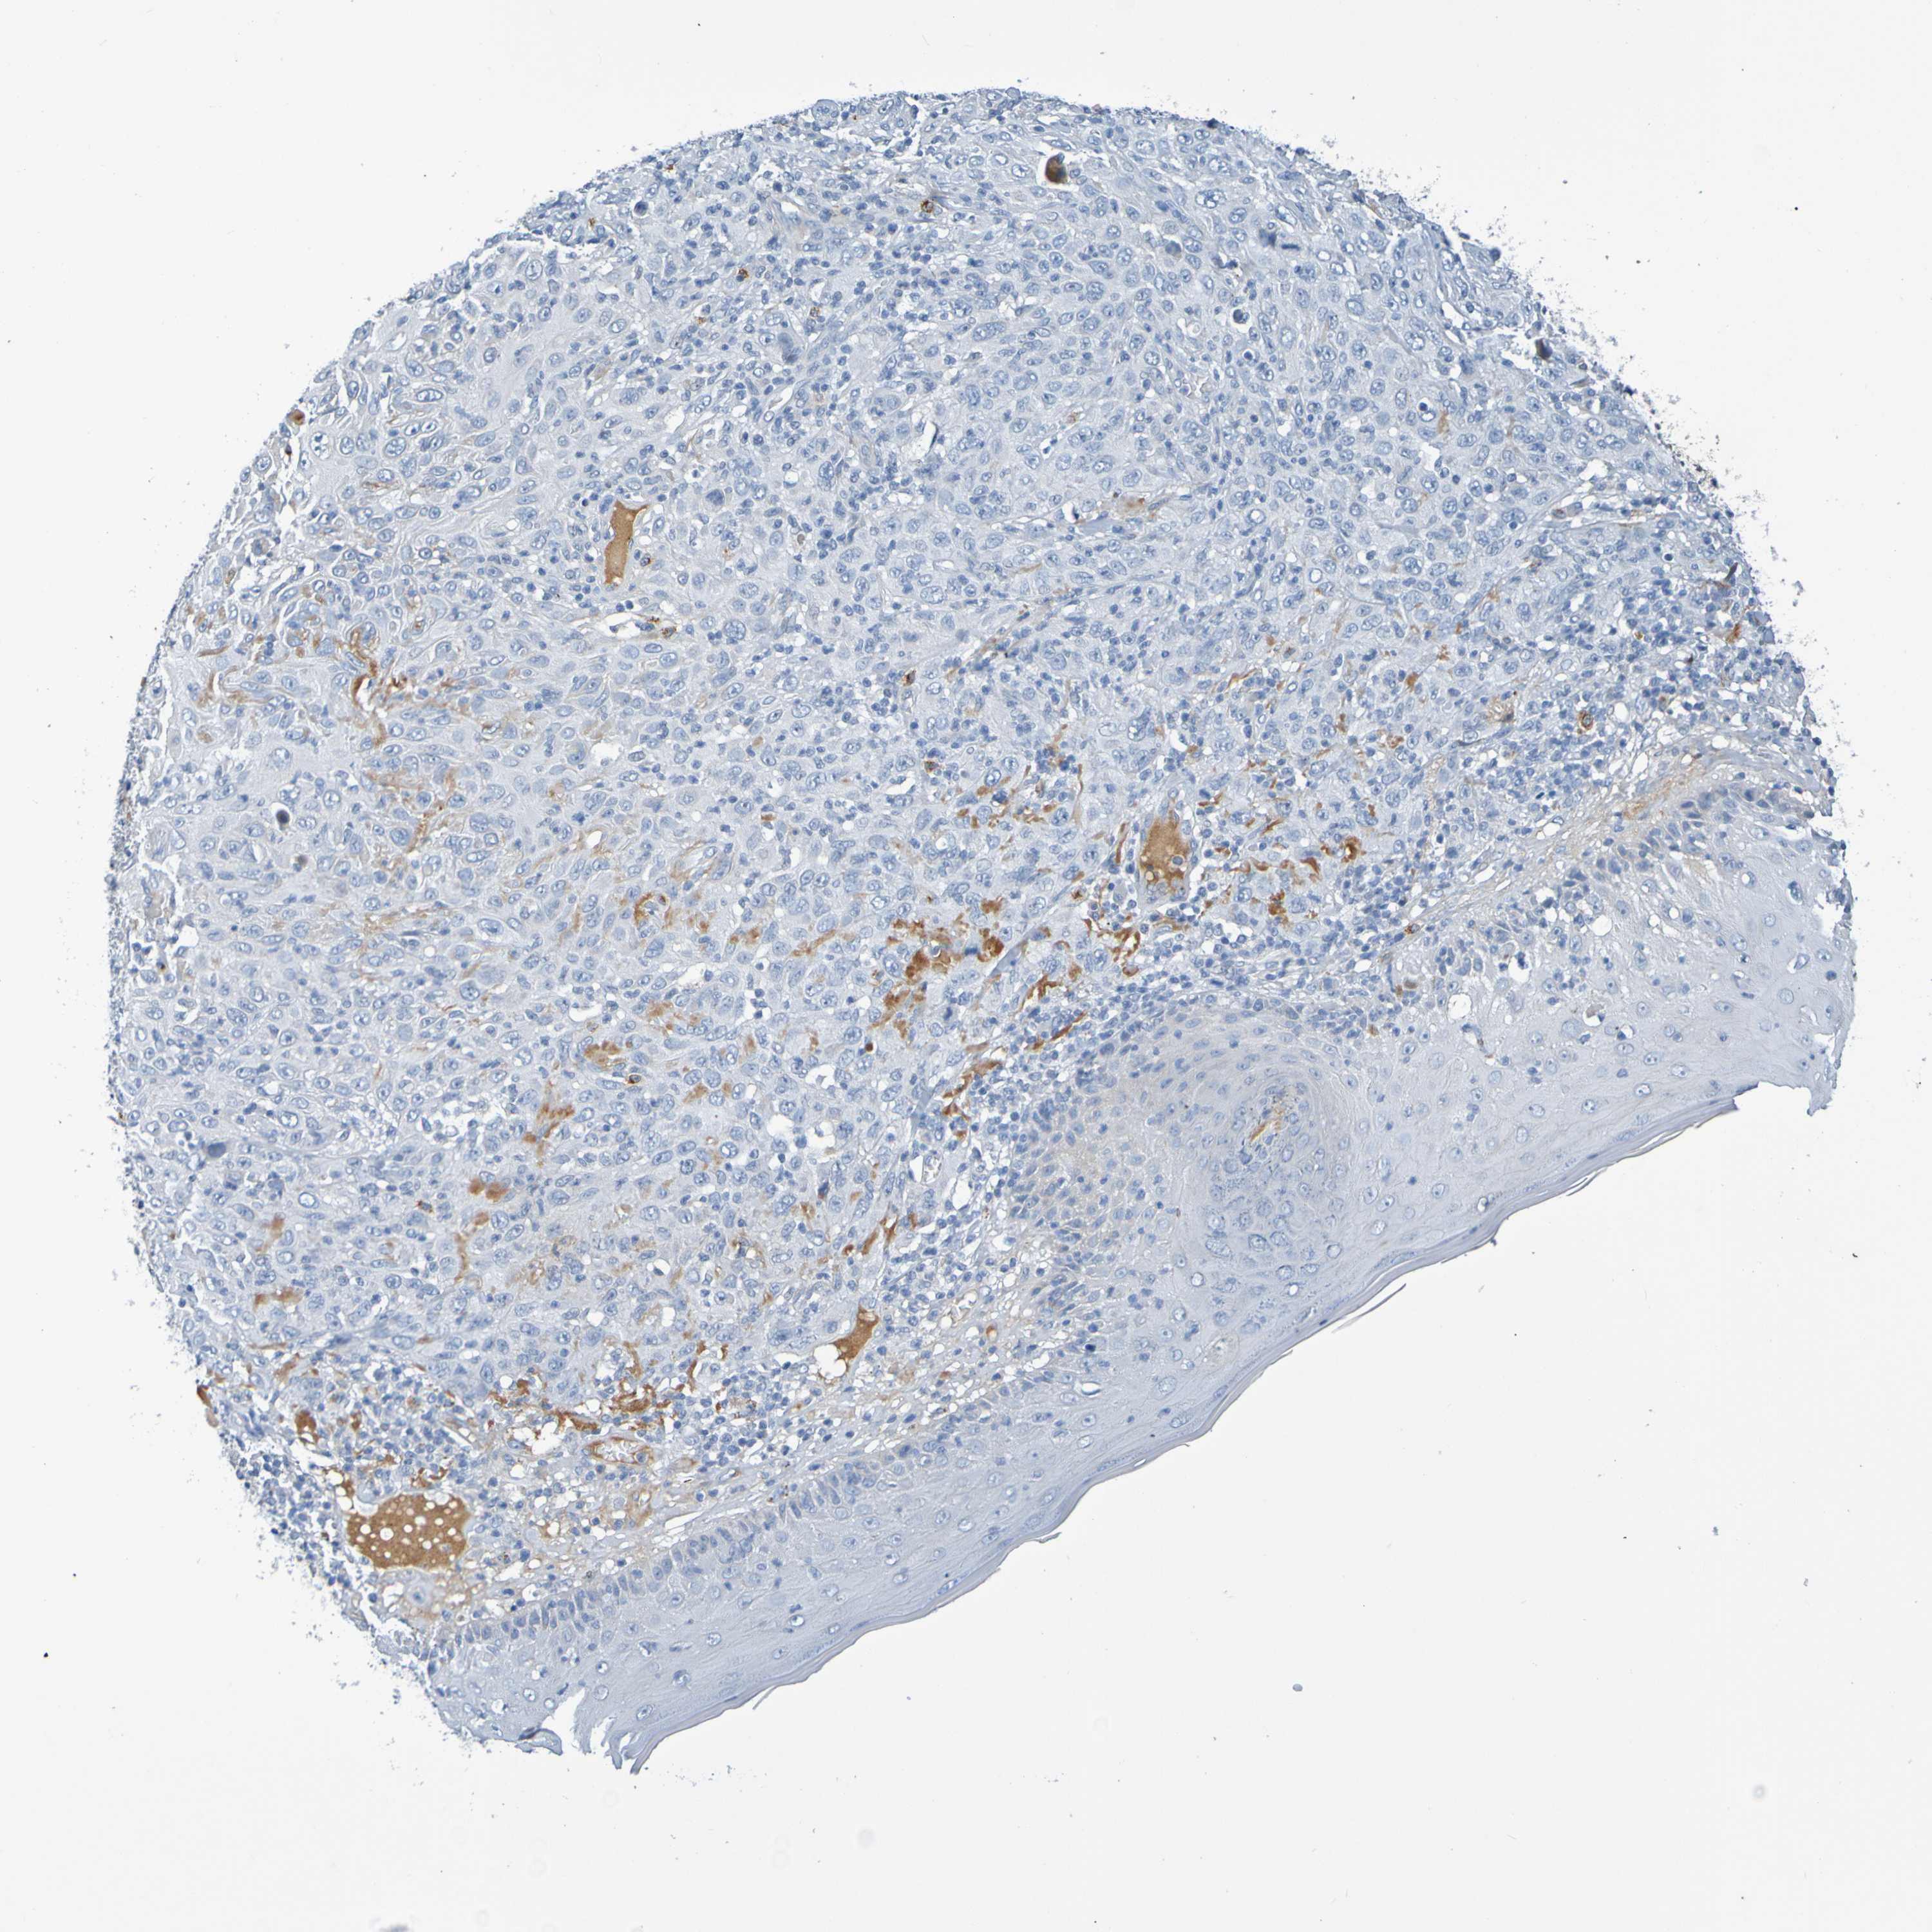

CANCER SKIN CANCER Show tissue menu

Basal cell and squamous cell cancer

SKIN CANCER - Protein expressioni

A mouse-over function shows sample information and annotation data. Click on an image to view it in a full screen mode. Samples can be filtered based on level of antibody staining by selecting one or several of the following categories: high, medium, low and not detected. The assay and annotation is described here.

Each image is clickable and will lead to virtual microscopy that enables deeper exploration of all samples and also displays staining intensity scores, fraction scores and subcellular localization as well as patient and tissue information for each sample.

Antibody HPA071391

Antibody CAB013120

Basal cell carcinoma

Squamous cell carcinoma, NOS